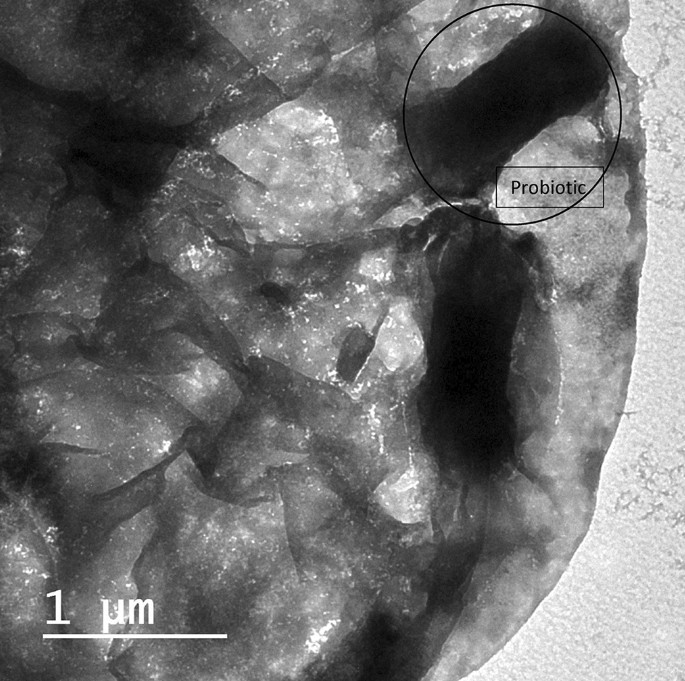

Vitis vinifera (Syrah grape) red grape seeds were received as production sachets from the manufacturer Ganklees factory (Alexandria Governorate, Egypt). The extraction of red grape seeds has been prepared at Packaging Materials Department, Chemical Industrial Research Institute (National Research Centre, Egypt). The extraction method used in this study was similar to the method explained by El-Sayed et al.14. 200 g of grape seed powder using a weighing balance (Pyrometro, Malaysia) was extracted with 800 ml of ethanolic solvent in a flask (ethanol: water, 70:30 (v/v) under constant agitation in a rotary shaker (Certomat Model S II, Sartorius, Goettingen, Germany) at 200 rpm, 45 °C, for 2 h. This was later centrifuged (Eppendorf Model 5810 R, Hamburg, Germany) at 5000 rpm for 10 min and subsequently decanted. Following, the residue was re-extracted for 2 h, and the supernatants were evaporated using a rotary evaporating instrument (Buchi Rotavapor R-215, Flawil, Switzerland) at the set pressure of 175 mBar, temperature of 52 °C, and speed of 95 rpm to remove the solvent. The ethanolic extract of grape seed powder was collected and stored in a glass container under frozen conditions14. The selected probiotic strain Lacticaseibacillus rhamnosus (NRRL B-442) was provided from the Dairy Microbiology Laboratory (Food Industries and Nutrition Research Institute, National Research Centre, Egypt), and grew in MRS broth and was incubated for 48 h at 37 °C anaerobically. The bacterial cells were obtained after centrifugation at 5000 rpm for 15 min using a cooling centrifuge at 4 °C14. The obtained cells were washed by saline solution (0.9% NaCl) and centrifuged at the same conditions. GSE Nano emulsion of 3% concentration with obtained probiotic cells in count around 107 CFU/ml incorporated in a prepared jelly candy base formula (under patent registration no. 2021/976; Ministry of Scientific Research, Academy of Scientific Research and Technology, Egypt). GSE Nanoemulsion of 3% concentration with obtained probiotic cells in count around 107 CFU/ml incorporated in a prepared jelly candy base formula. Firstly, probiotics jelly candy was prepared by heating water with honey and mixing well in a brass pan. After that, add the gelation solution by (melting the gelatin in warm water at 70 °C) to the previously prepared syrup and mix it well. Oleic acid, present in Tween® 80, was added when the temperature reached 90 °C. The temperature of the mixture decreased to 40 °C before adding the previously developed formula that was designated by probiotic cells of L. rhamnosus with 3% GSE nanoemulsion14. Morphological study of the probiotic jelly candy supplemented with nanoemulsion grape seed extract (GSE) was evaluated using transmission electron microscopy (TEM) (Fig. 1).

Transmission electron microscopy (TEM) showing part of a piece of jelly candy with probiotic bacteria (black circle) inside.

Transmission electron microscopy (TEM) image analysis in (Fig. 1), showing a bacteria cell Lacticaseibacillus rhamnosus (NRRL B-442) (black circle) covered by a smooth and homogeneous surface part of a piece of jelly candy.

A smooth and homogeneous surface of jelly candy under transmission electron microscopy (TEM) as revealed in (Fig. 1). The addition of oleic acid to the interior components of the developed formula of jelly candy could cause a change in its morphological surface. In addition, it is suggested that the availability of certain fatty acids in a developed formula is a factor that contributes to maintaining the probiotic bacterial cell wall morphology inside the jelly candy and the protection in contradiction of acidic conditions in the oral cavity45.